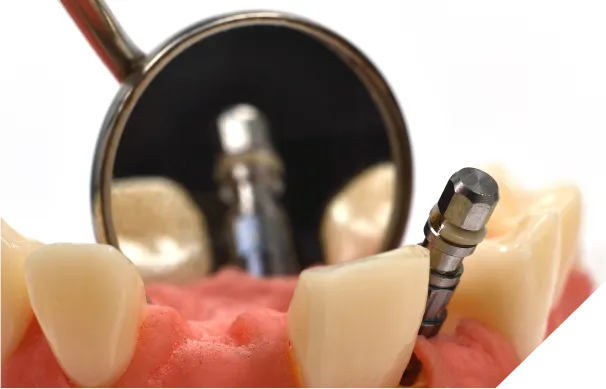

手術中の偶発的な事故

下顎には太い神経と血管が通る管(下顎管)が、上顎の奥には上顎洞という空洞があります。インプラントを埋め込む際にこれらを傷つけてしまうと、唇の麻痺や多量の出血といった重大な合併症を引き起こすリスクがあります。